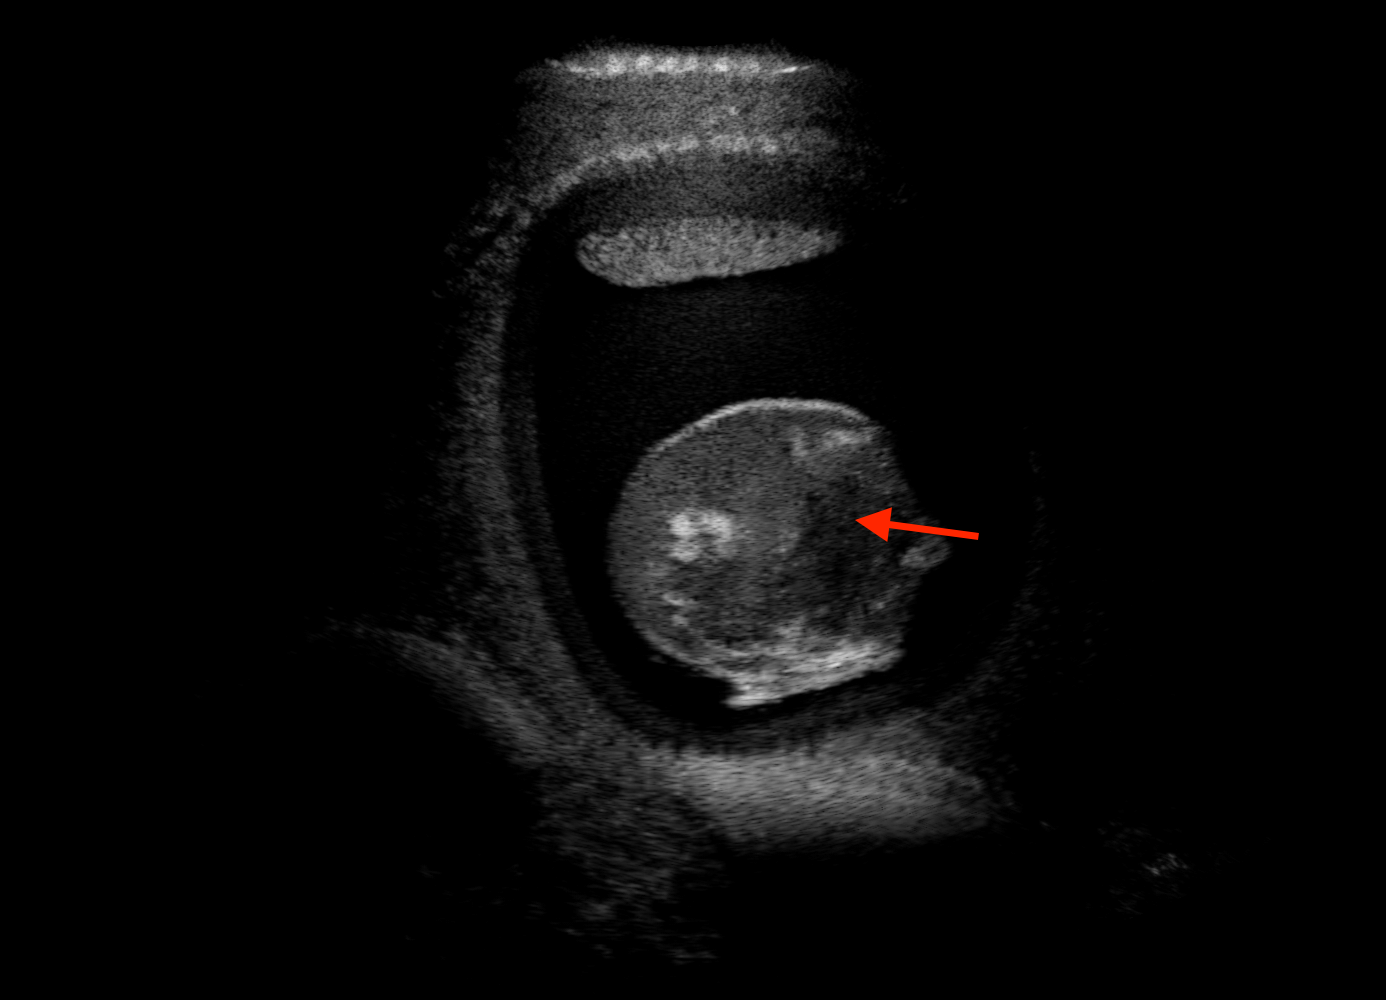

Qualitative evaluation.

Fig. 2 depicts the qualitative results for all the models mentioned above, with arrows pointing at structures relevant to discussion points below. The visual results of the ablated variants of SA2H show substantial quality degradation compared to the full SA2H model, demonstrating the importance of each proposed architectural contribution. Given only segmentation map in the network input, SA2H-att fails to generate acoustic shadows, e.g. those cast by the ribs. Detailed structures such as the cervical vertebrae are blurred out in the SA2H-concat results, which also contain hallucinated structures mainly due to insufficient preservation of input information along the encoding-decoding path. With SA2H-conv, checkerboard artefacts are observed due to the lack of proposed additional stride-1 convolutional layers. SA2H-noise without any explicit noise input is seen to be sub-optimal at generating textural details. The baseline method NSA2H fails to preserve anatomical structures and acoustic shadows in all cases, while the simulated textures also show significant artefacts such as checkerboard patterns. Realism of different simulation aspects may become relevant given different clinical applications and scenarios. For instance, improved structural preservation, e.g. with the hyperechoic bony structures such as the skull and the ribs, of the final model over its ablated variants and NSA2H may prove relevant in fetal head measurements, while the textural improvements facilitating screening fetal organ maturity, e.g. lungs. Compared to the silver-standard model LSA2H with a low-quality rendered image as additional input, SA2H is seen to be on par in structural preservation. Note that shadowing on homogenous regions (e.g. the rib shadowing on the homogenous lung region on the 4th column of Fig. 2) with our proposed method SA2H is represented more faithfully compared to LSA2H, whereas shadows on structurally complex regions (e.g. the skull shadowing around the heart and surrounding tissues on the 3rd column of Fig. 2) are suboptimal with our SA2H. Therefore, one may have to evaluate our method given particular simulation tasks, e.g. its clinical validity for fetal heart exams. However, even with low quality rendered images, LSA2H leads to artificial enhancements of intensities, lack of acoustic shadows, and low-quality textures especially near the probe, for which SA2H yields satisfactory results as illustrated in Fig. 2.

For the interpretation of the local errors, sample spatial p error maps are depicted in Fig. 3 for LSA2H, NSA2H, and SA2H for the middle two examples shown in Fig. 2. Both images generated by NSA2H have a lot of missing structures and accordingly have high error almost all over the map. Artificial skull enhancement with LSA2H is seem to evoke large p error, as shown in the corresponding error map, whereas the bright spots in the error map of SA2H reflect some hallucinated shadows and structure in the brain. All of above mentioned regions of interest are marked by red arrows. In the bottom example, SA2H fails to generate faithful content at the bottom region marked by red circles, which is well indicated by the error map as well.